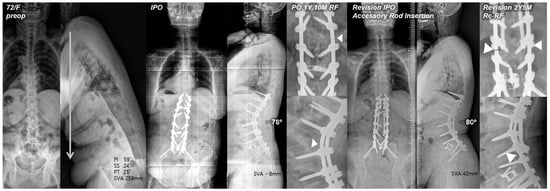

4.3. Bilateral Rod Replacement with Accessory Rod Insertion

Posterior reinforcement at the PSO site with multiple-rod fixation for appropriate load distribution is a crucial preventive method for RF. Numerous finite element models have demonstrated the effectiveness of additional rods in reducing stress on the primary rods across the osteotomy site [25,26]. Several clinical studies also have reported that multiple-rod fixation reduced the occurrence of RF and increased the stability at the osteotomy site [3,9]. A biomechanical study by Scheer et al. [27] that analyzed revision strategies for RF in PSO reported that multiple-rod fixation could restore stiffness and prevent fatigue in revision constructs. Therefore, multiple-rod fixation should offer proven biomechanical stability in terms of revision for RF. However, RF can still occur even with reinforcements. In our study, re-RF occurred in one of 22 patients in the RR + AR group. Interestingly, instead of occurring at the PSO site, it occurred just below each junction between the distal end of the AR and the primary rod (Figure 3). We believe that, in the application of multiple rods, connecting the distal end of the AR to the previous instrumentation at the S1–2 area could potentially offer increased stability in conjunction with L5-S1 interbody fusion and sacropelvic fixation, and further studies to confirm this are warranted.

Figure 3. Pre- and postoperative standing radiographs of a 72-year-old female patient. After T10-S1 posterior instrumentation with PSO on L2, and ALIF on L5-S1, optimal sagittal balance was achieved (SVA, −8 mm; TK, 27°; LL, −78°; PI, 60°; PT, 12°; SS, 48°). At 1 year and 10 months after primary deformity correction, RF (right rod) occurred at L2–3. At 2 years and 5 months following revision surgery with bilateral rod replacement and accessory rod insertion, re-RF occurred at L4–5. White triangles indicate sites of RF.